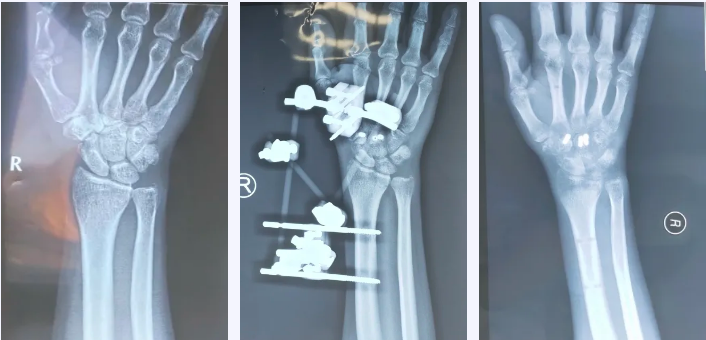

医生为了方便记忆,总结为“舟月三角豆,大小头状钩。”腕骨骨折是一种常见的骨科疾病,多因跌倒或暴力导致腕部受到剧烈应力撞击,发生骨折。北京燕化医院康复医学科近期便接收了一位腕骨骨折的患者。43岁的徐先生不小心撞伤右手,经检查,发现右手腕骨头状骨、小多角骨、舟状骨骨折。

2021年7月16日于外院进行“腕掌关节脱位切开复位内固定术+腕骨骨折切开复位内固定术+外固定架固定术”。

9月23日,来我科就诊,以进一步开展早期康复。就诊时,腕部有明显肿胀,关节活动受限,局部有压痛,患者愁眉苦目,经问诊,了解到其工作需具备较高动手能力,担心影响未来工作。为消除患者顾虑,康复医学科为其制定了针对性康复训练计划,以尽快恢复部分运动功能,扩大关节活动度,增加肌肉力量等。(下图为患者手部影像资料)